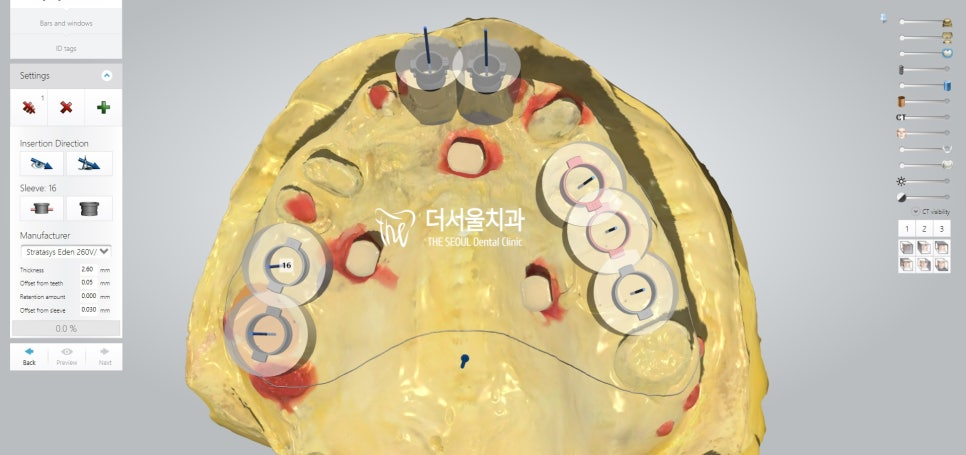

계산된 위치에 맞춰 픽스쳐를 심어드렸습니다.

개수가 많기 때문에 걱정이 되었지만,

미리 제작된 가이드를 사용하여 수술을 진행하였더니

즉시식립 임플란트 과정을

정확하고 안전하게 끝마칠 수 있었습니다.